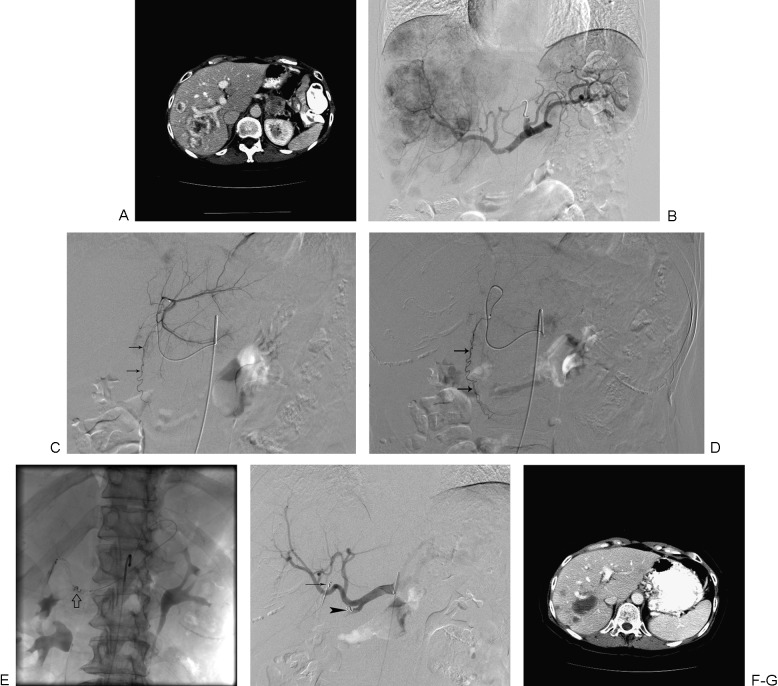

Neuroendocrine Liver Metastasis

- Somatostatin receptor-based imaging techniques like gallium-68 dotatate PET/CT with high sensitivity in NET detection

- Telotristat, recently FDA-approved drug in ameliorating symptoms of patients with poorly controlled carcinoid syndrome

- 177Lu-Dotatate, a radiolabeled somatostatin analog, with significant improvement in PFS of patients with advanced midgut NET

- Molecular-targeted therapies such as everolimus and sunitinib with antitumor activity to improve PFS in advanced PNET